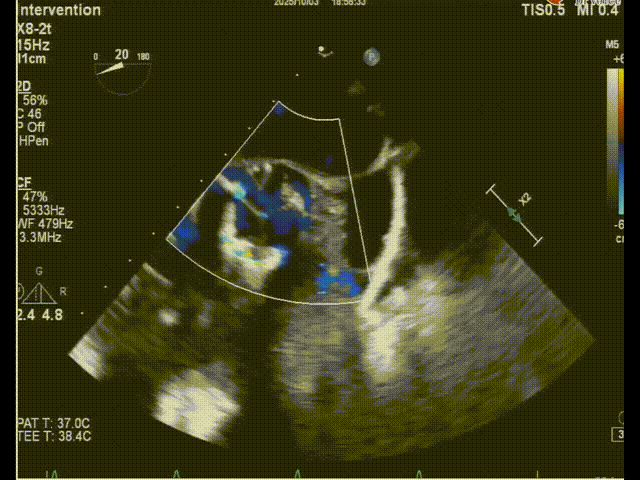

术后食道超声-短轴color

术后食道超声-长轴-color